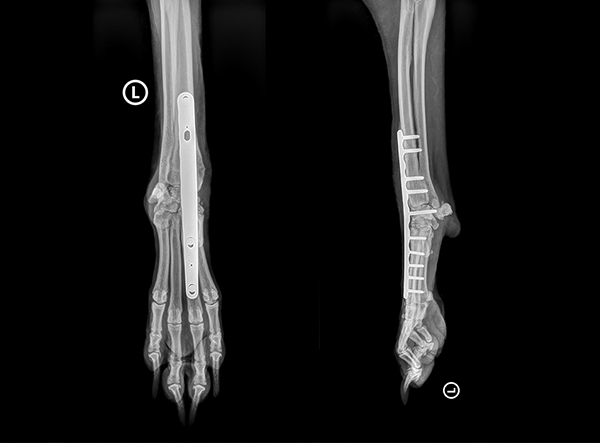

Radiographic Outcome

Post-operative X-rays confirmed excellent implant positioning, strong bicortical screw fixation, and optimal alignment. Jack’s forelimb was now set for a solid and pain-free recovery.